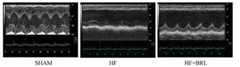

Fig. 3 reduces heart failure rat heart muscle apoptosis for BRL37344;

Fig. 4 is myocardium p53, increase SIRT1 for BRL37344 reduces;

Fig. 5 improves heart failure rat cardiac function for BRL37344;

In the Rat of Myocardial Infarction model, excited beta 3 receptor can increase myocardial cell SIRT1, and reduces p53 and express, and improves cardiac function, brings into play anti-apoptotic effect.Ligation rat ramus descendens anterior arteriae coronariae sinistrae causes the heart infarction model.Lumbar injection BRL37344 1mg/kg/day, it is ultra to be heart b after 4 weeks.Core dirty tissue detection apoptosis (tunel method) and SIRT1, p53 expresses (western blot).It is dirty to core, the measurement of left ventricle heavy with anharmonic ratio value (LVW/BW) whole-heartedly.Result such as Fig. 3~5, BRL37344 reduces myocardium p53, and increases SIRT1, reduces apoptosis of cardiac muscle, reduces heart failure rat LVW/BW, reverses myocardial hypertrophy, improves cardiac function.